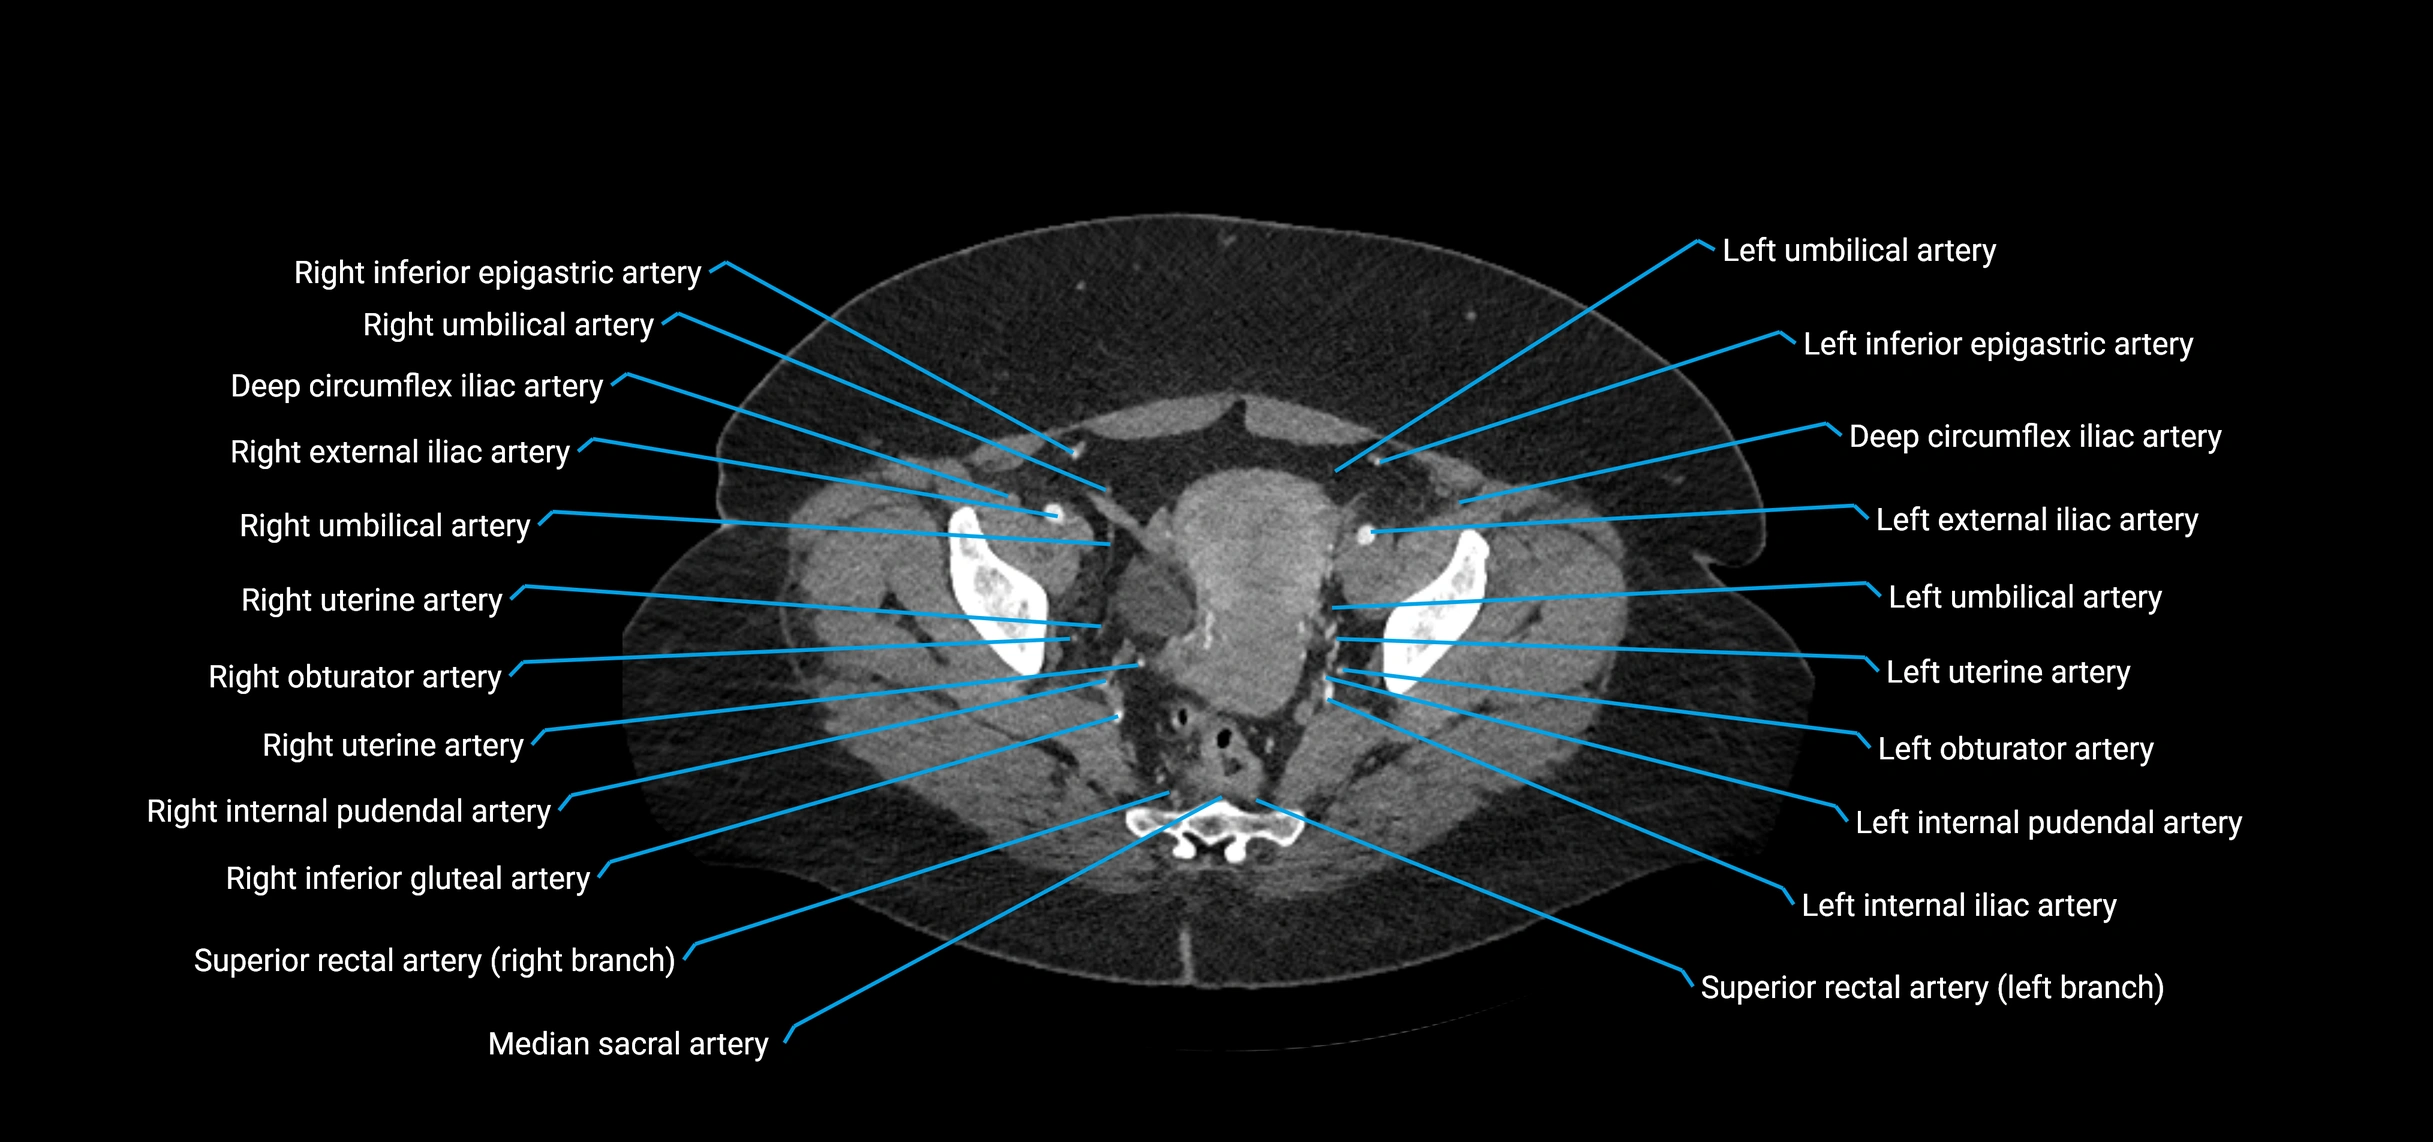

CT Appearance

Non-contrast CT:

• Appears as a tubular soft tissue structure anterior to vertebral bodies

• Calcified atherosclerotic plaques appear as hyperdense foci along the wall

• Useful for screening abdominal aortic aneurysm (AAA) size and mural calcification

Contrast-enhanced CT (CTA):

• Gold standard for abdominal aortic imaging

• Provides excellent detail of lumen, wall, aneurysm, thrombus, and branch vessels

• Multiplanar and 3D reconstructions help in aneurysm measurement, stent graft planning, and dissection evaluation

• Detects acute rupture, traumatic injury, or occlusion with high sensitivity